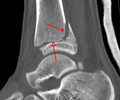

A triplane fracture of the ankle as seen on CT